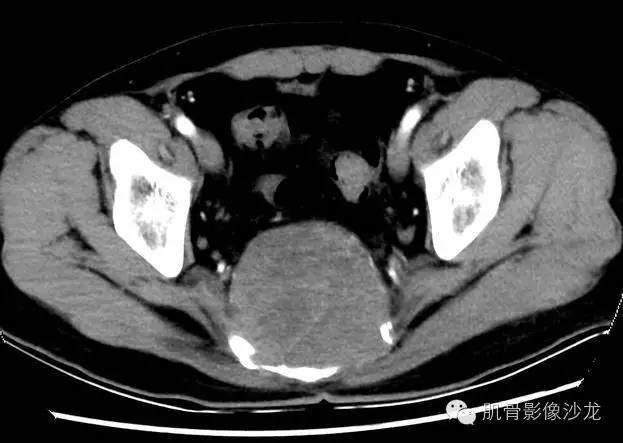

影像表现:骶骨中下部见溶骨性骨质破坏,破坏区见软组织肿块影,边缘无硬化,其内密度不均,可见散在钙化灶,未见骶管、骶孔扩大;强化轻,未见明显坏死。

1、发病部位,有利于脊索瘤的诊断,不利于骨巨的诊断。

2、内可见钙化,有利于脊索瘤的诊断,不利于骨巨的诊断。

4、强化轻,未见明确坏死,未见骶管、骶孔扩大;不利于神经源性肿瘤的诊断。

最后病理:脊索瘤。